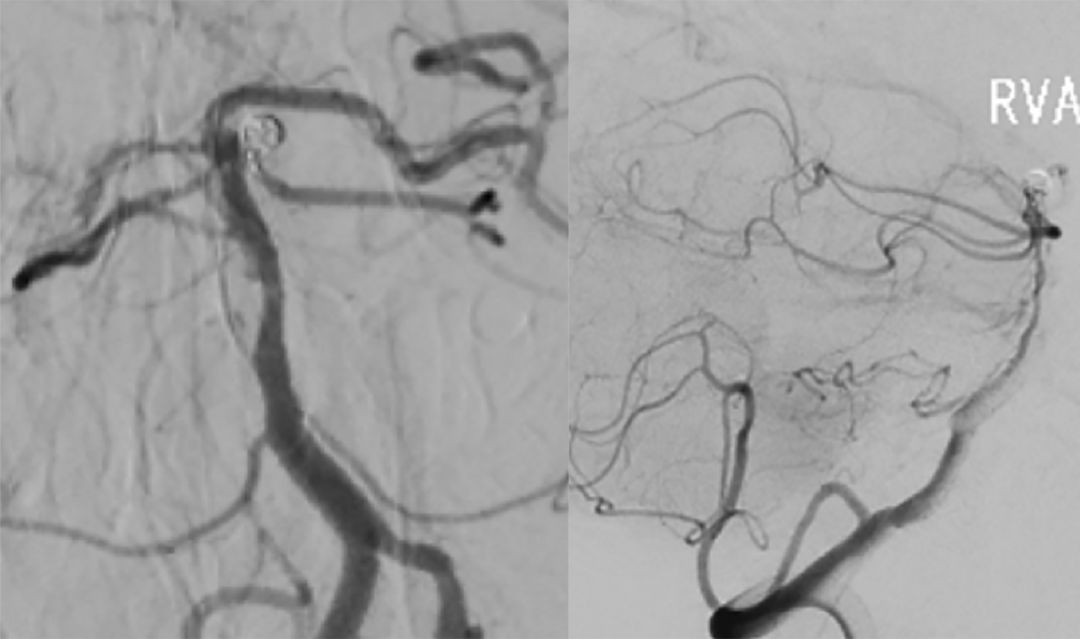

7. 术后造影显示动脉瘤完全栓塞,载瘤动脉通畅(图13)。

图13